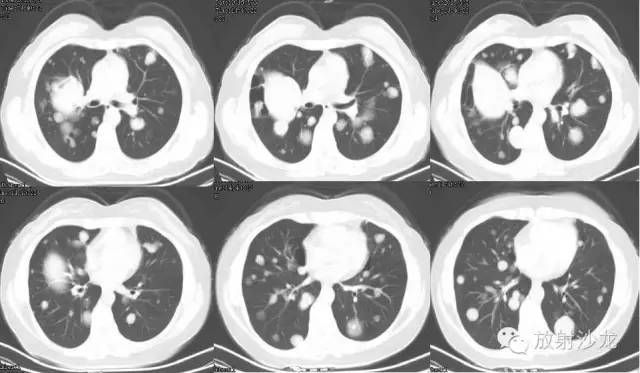

【影像表现】

双侧胸廓对称,纵隔居中。双肺可见散在多发大小不等类圆形软组织密度影,密度欠均,边界较清,最大者约5.32cm*7.88cm*6.75cm,右肺中叶、下叶可见一不规则形透亮影,内无肺纹理,纵隔未见明显肿大淋巴结,胸膜无增厚,右侧胸腔内可见弧形液体密度影。

双肺多发结节占位病变

右肺中下叶肺大泡

右侧胸腔积液